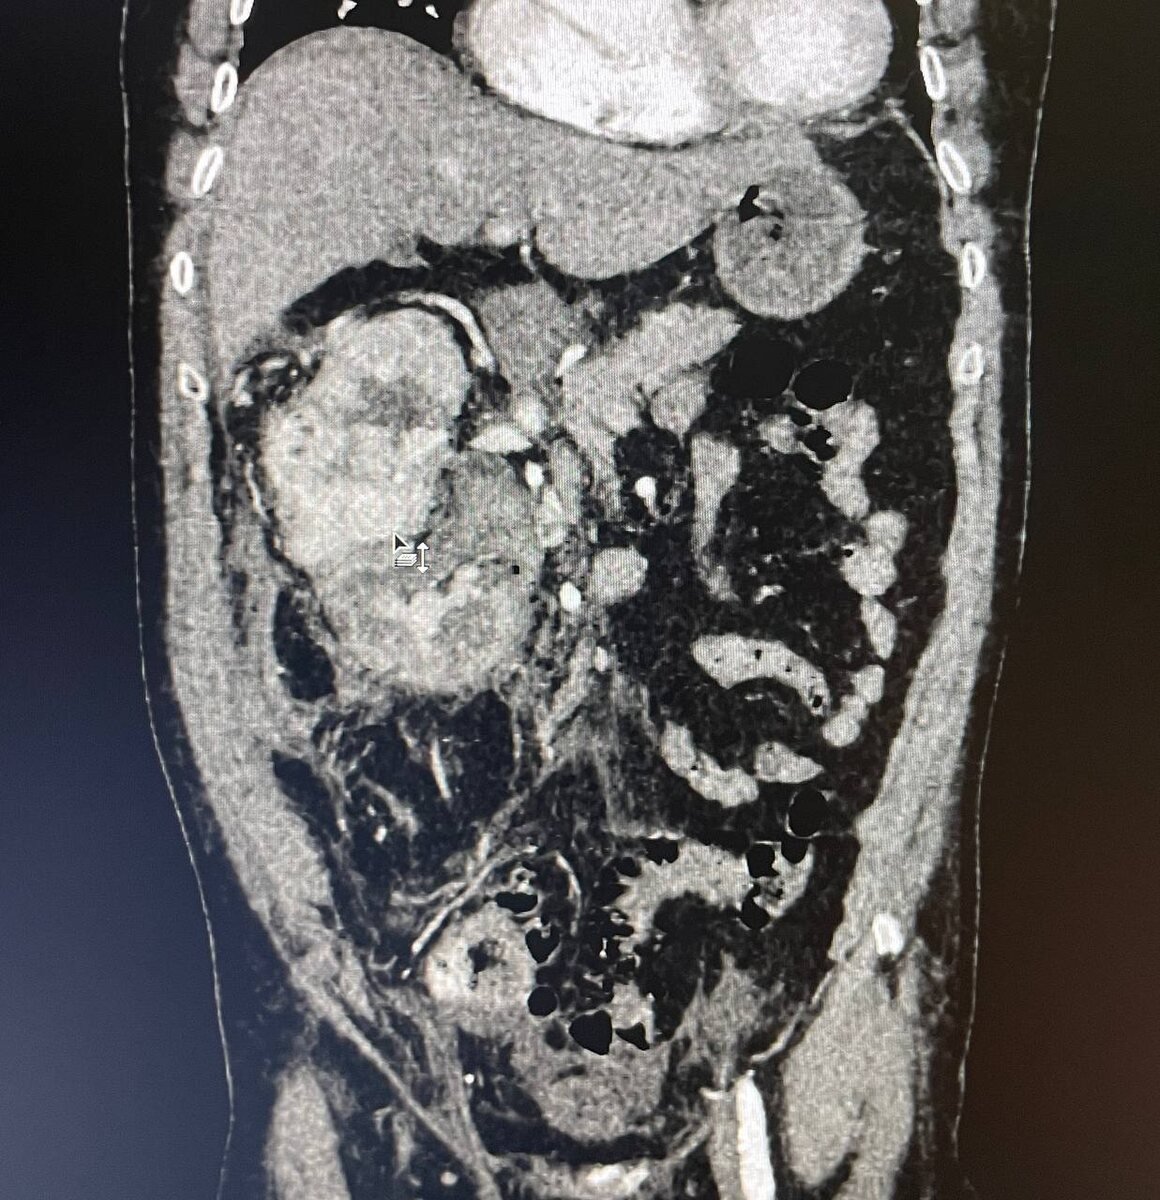

Во II, III сегментах правой почки определяется крупное гиперваскулярное образование единственной правой почки (1 фото, в анамнезе агенезия левой почки), с инвазией в ЧЛС (2 фото), с опухолевым тромбозом почечной вены, с пролапсом опухолевых масс в просвет нижней полой вены (3 фото). Отёк паренхимы правой почки со снижением её выделительной функции. Каликопиелоэктазия с геморрагическим содержимым в чашах и лоханке. Остаточная забрюшинная гематома справа (образовалась после попытки установки нефростомы, опухолевые массы в ЧЛС помешали манипуляции, оставленную нефростому можем видеть вдоль заднего листка фасции Героты - выполняет функции дренажа сформировавшейся забрюшинной гематомы).

Также определяется гиперваскулярное образование в латеральной ножке правого надпочечника (mts?, 4 фото). Диффузные изменения печени. Липоматоз поджелудочной железы. Асцит. Дивертикулёз сигмовидной кишки без признаков дивертикулита. Атеросклероз брюшного отдела аорты и подвздошных артерий. ДДЗП.